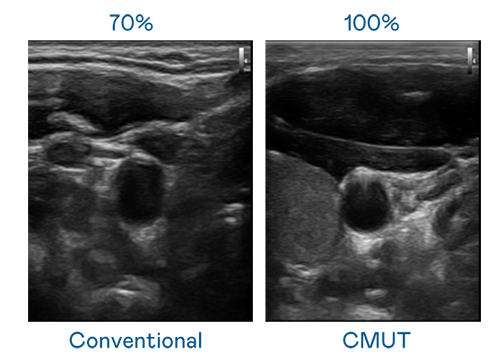

CMUT 技术是一种用电容式微机电元件来产生超音波讯号的技术。与传统 PZT 压电式技术相比,CMUT 频宽增加 30%,更宽频的超音波讯号让影像解析度大幅提升,是实现高影像品质医疗超音波扫描、促进精准医疗发展的关键技术。

超音波影像的解析度高低,首先取决于探头能发出的讯号频宽。博天堂918 CMUT 可提供高清晰的超音波讯号,提供高频宽、高灵敏度、影像纹理细节更高的超音波影像,协助医护人员缩短影像判读时间及利用精准的医疗影像进行诊断。